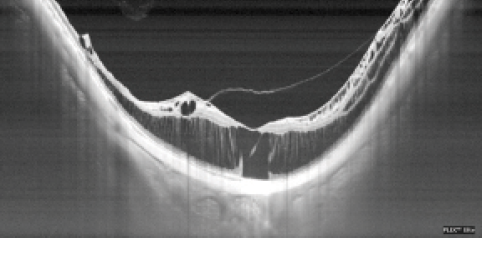

Figure 1. A thin slice-volume scan on OCT demonstrates the presence of a micromacular hole in an eye with myopic retinoschisis and FRD.

We also emphasize the importance of precise examinations using optical coherence tomography (OCT) during follow-up of MTM. To detect early FRD or micro-MH, thin-slice volume scans of OCT are useful to detect microstructural changes in the fovea (Figure 1). Swept-source OCT is also helpful to evaluate a wide area of the vitreoretinal surface for the presence of partial or complete posterior vitreous detachment (PVD), ERM, disruption of ILM, and determination of the thickness of the nerve fiver layer before vitrectomy (Figure 2).